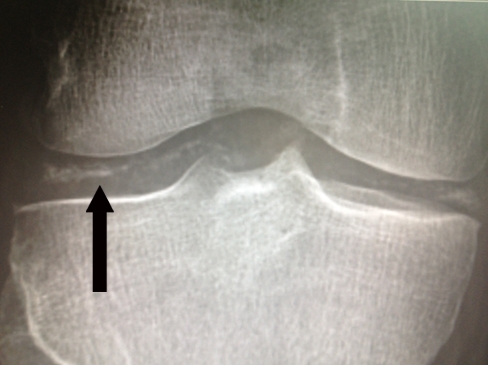

Osteoarthritis

.,

Knee x-ray findings in patients with osteoarthritis include joint space narrowing, subchondral sclerosis, osteophyte formation, and subchondral cysts.